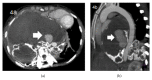

Giant cell tumor of bone (GCT) is a rare, locally aggressive neoplasm characterized by the presence of giant cells with osteoclast activity. Its biology involves the overexpression of the Receptor Activator of Nuclear Factor kB Ligand (RANKL) by osteoclast-like giant cells and tumor stromal cells, which has been shown to be an actionable target in this disease. In cases amenable to surgical resection, very few therapeutic options were available until the recent demonstration of significant activity of the anti-RANK-ligand monoclonal antibody denosumab. Here we present a case of a patient with advanced GCT arising in the spine, recurring after multiple resections and embolization. Following initiation of denosumab, which resulted in unequivocal clinical improvement, computed tomography of the chest done for reassessment purposes revealed an intratumoral pseudoaneurysm by erosion of the aorta, further corrected by endovascular approach and stent placement. Patient had an unremarkable recovery from the procedure and continued benefit from therapy with denosumab and remains on treatment 24 months after the first dose.